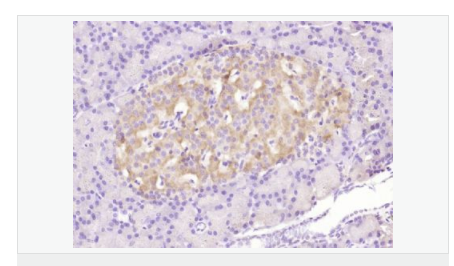

| 產(chǎn)品應用 | WB=1:500-2000 ELISA=1:5000-10000 IHC-P=1:100-500 Flow-Cyt=3μg /test (石蠟切片需做抗原修復) not yet tested in other applications. optimal dilutions/concentrations should be determined by the end user. |

| 免 疫 原 | KLH conjugated Synthesised phosphopeptide derived from human Bax around the phosphorylation site of Ser184:TA(p-S)LT |